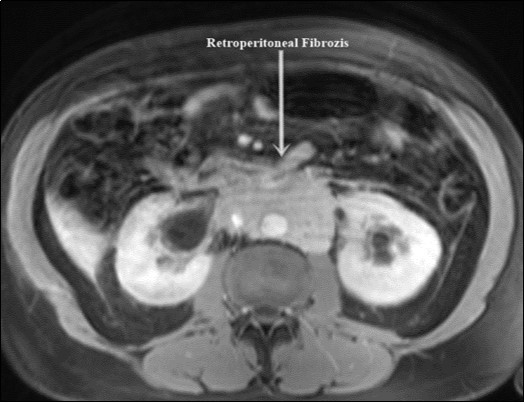

A 58-year-old male patient was admitted to our clinic with complaints of severe weakness, loss of appetite and decreased urine volume. The patient had chronic, mild lower urinary tract symptoms. Serum creatinine level of the patient was 5.3 mg/dl and he had no additional diseases except hypertension. Bilateral grade 3 hydronephrosis and moderate residual urine was revealed in urinary ultrasonography. A transurethral foley catheter was inserted and the patient was admitted to the internal medicine intensive care unit with the diagnosis of acute renal failure due to infravesical obstruction. During follow-up, abdominal magnetic resonance imaging (MRI) was performed due to oliguria and high serum creatinine level (Figure 1). Magnetic resonance imaging revealed a mass of approximately 88x49 mm in the axial plane at the renal artery outlet level, consistent with retroperitoneal fibrosis, tuberculous lymphadenitis or lymphoma. Grade 3 pelvicaliectasis was seen in bilateral kidneys. The descripted lesion was observed in paraaortic area (except posterior). Tru-cut biopsy was planned with no evidence of malignancy on positron emission tomography. Tru-cut biopsy reported as connective tissue. Bilateral double-J ureteral stent was placed endoscopically to patient who was diagnosed as idiopathic retroperitoneal fibrosis (Figure 2). At the same time, alpha-blocker treatment was started. Creatinine levels decreased to normal after five days and normal volume voiding was observed after removal of foley catheter. The patient was started on glucocorticoid therapy which was foreseen to last for 1 year. After 2 months, PET imaging showed the decreased mass size and metabolic activity. Thereafter bilateral ureteral double-J stents were removed endoscopically. Ultrasonographic imaging showed no hydronephrosis after 7 days of catheter removal and the patient was recommended to continue glucocorticoid therapy and was followed up.

Figure 1.Retroperitoneal fibrosis involving both ureters.